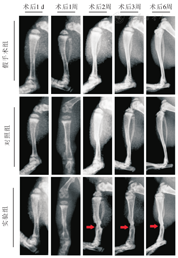

术后1 d小腿未见软组织肿胀,胫骨未见明显异常显影;术后1周未见软组织肿胀,胫骨移植区可见骨皮质周围高密度影形成;术后2~3周移植区胫骨纤细、髓腔狭窄,上下端类骨质生成(图2红色箭头所指部位);术后6周胫骨移植区胫骨纤细、髓腔狭窄情况仍存在,而上下端类骨质吸收硬化(图2)。

术后1 d小腿未见软组织肿胀,胫骨未见明显异常显影;术后1周小腿软组织稍肿胀,胫骨移植区可见骨皮质周围高密度影形成;术后2~3周可见胫骨移植区局部骨膜反应,未见髓腔狭窄;术后6周胫骨移植区未见明显异常(图2)。

术后所有X线片未见小腿周围软组织肿胀,未见胫骨骨质异常表现(图2)。